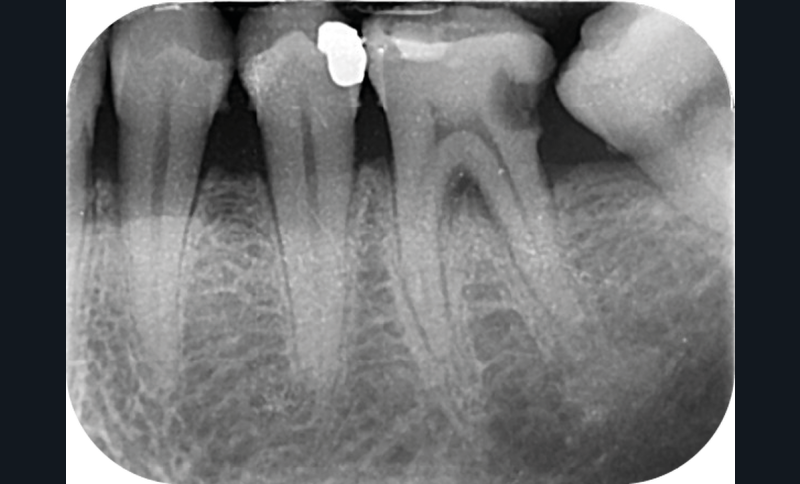

La version des dents distales peut aussi avoir des conséquences parodontales désastreuses : sur un parodonte réduit, une hypermobilité peut se développer, une poche parodontale peut aussi apparaître. Chez un patient parodontal, un « effet domino » est possible, des extractions non compensées diminueront donc le pronostic des dents restantes (fig. 7 à 9).